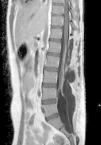

El meningioma de células claras es una variedad infrecuente de meningioma. Se describe el caso de un meningioma espinal multifocal de células claras presente en una paciente de 20 años de edad. Clínicamente refiere lumbalgia de aproximadamente 2 años de evolución. En el estudio de resonancia magnética nuclear (RMN) se evidencia gran tumoración lumbosacra, que ocupa el canal raquídeo de L4 a S2, asociada a 2 lesiones satélites en la región lumbar. Una tumoración intra-extradural fue resecada quirúrgicamente, confirmándose el diagnóstico anatomopatológico de meningioma de células claras. Se resecan así mismo ambas lesiones satélites con idéntico diagnóstico histológico.

Clear cell meningioma is a rare morphological form of meningioma. This case report describes a very rare case of multifocal clear cell meningioma in the sacral and lumbar spine. The patient was a 20-year-old female who presented back pain. Magnetic resonance imaging (MRI) revealed a large tumour at L4 to S2 level associated with two, smaller, satellite tumours at the lumbar level. An intra-extradural tumour was surgically removed and the pathological diagnosis of clear cell meningioma was confirmed. Both satellite lesions were also resected and their histopathological diagnosis was the same.